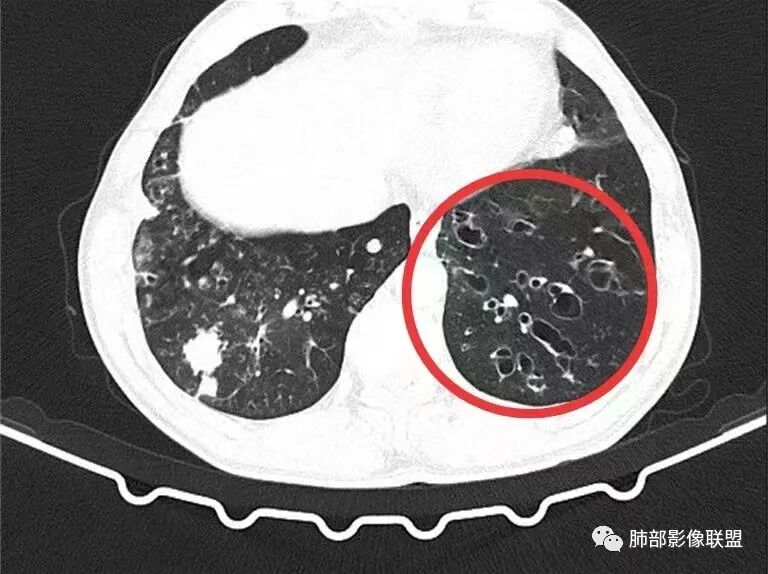

男性,56岁,清洁工,临床表现咳嗽咳痰发热。胸部影像:两肺散在斑片、结节及实变影,大部分沿气道分布,以下肺为著并伴发多发支气管扩张及囊腔影,实验室检查白细胞增高,考虑感染性病变,曲霉、铜绿及NTM。

56岁,工作性质:环卫工人。主诉:咳、痰、喘、发病一周。急性起病(或者慢病+AE),呼吸道感染症状。化验指标白细胞、中性、CRP明显升高。影像学显示多灶性,有柱状支扩,囊状支扩等结构肺病,责任细菌主要考虑铜绿假单胞菌,不排除合并其他细菌以阴杆为主;存在树芽影,发热,炎症沿支气管束分布,是否合并TB?真菌?;树芽伴发热支原体感染也要需要考虑进去;全肺多灶性炎症,部分病灶周围有晕,右上叶疑似反晕,内部疑似有丝,右下肺考虑存在粘液栓,加之环卫工工作性质,考虑霉菌,主要考虑曲霉。

两肺支扩,两肺沿支气管分布多发结节、树芽及团块,边缘模糊,部分支气管管壁增厚,考虑气道侵袭性曲霉菌,鉴别铜绿、奴卡、结核。

多发结节,部分结节边缘清楚,部分边缘模糊,支扩合并肉芽肿性炎,奴卡菌与曲霉之间选择。